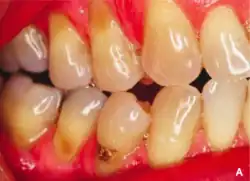

La abrasión dental es el desgaste mecánico no cariado de los dientes, debido a la interacción con otros objetos.[1] Afecta con mayor frecuencia a los premolares y caninos, generalmente a lo largo de los bordes cervicales.[2] Basándose en encuestas clínicas, los estudios han demostrado que la abrasión es el factor etiológico más común, aunque no el único, para el desarrollo de lesiones cervicales no cariadas (CLNC) cuya causa se debe frecuentemente a una técnica de cepillado incorrecta.[3]

La abrasión aparece habitualmente en la unión cemento-esmalte y puede estar causada por muchos factores que contribuyen en diferentes grados.[4]

El aspecto puede variar dependiendo de la causa de la abrasión, sin embargo, se presenta más comúnmente en forma de V causada por presión lateral excesiva durante el cepillado dental. La superficie es brillante en lugar de cariada, y a veces el reborde es lo suficientemente profundo como para ver la cavidad pulpar dentro del propio diente.

En cuanto a la presencia de pérdida cervical no cariada debida a la abrasión, puede derivar en consecuencias y síntomas tales como: aumento de la sensibilidad dental al calor y al frío, aumento de la retención de la placa que dará lugar a caries y a enfermedad periodontal, dificultades con los aparatos dentales tales como los retenedores y las prótesis dentales al embonar con el diente, y, también puede ser estéticamente desagradable para algunas personas.[3]